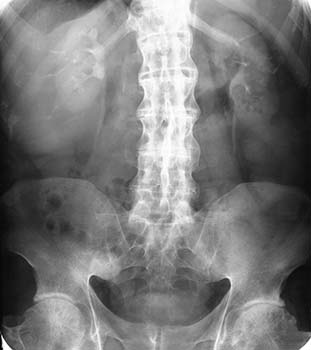

X-ray of spine & MRI studies: Severe unilateral sacroilitis or moderate bilateral sacroilitis wherein there is inflammation of the hip bones.

X-ray showing Bamboo Spine

in a patient with Ankylosing Spondylitis - Genetic marker blood tests are the major diagnostic tools. More than 95% of people who have been diagnosed with Ankylosing Spondylitis are HLA-B27 positive.